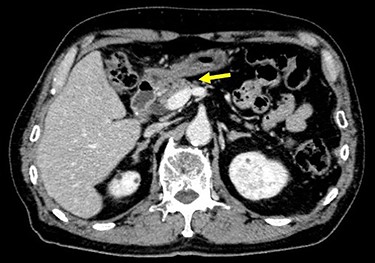

The patient received S-1, oxaliplatin and trastuzumab (SOX+Tmab) (S-1; 120 mg/body/day, days 1–14, oxaliplatin; 130 mg/m2, day 1, trastuzumab; 8 mg/kg for the first week and then 6 mg/kg every week thereafter, day 1). After finishing a total of four cycles of neoadjuvant chemotherapy, the efficacy was evaluated by CT, which showed significant shrinkage of the tumor at the antrum and detachment from the pancreatic head, with no enlarged lymph nodes (Fig. 6). Follow-up EGD revealed a very small ulcerative lesion at the antrum (Fig. 7). The serum level of CEA had decreased to 9.0 ng/ml.

CT after the NAC had been completed showed a significantly shrunken tumor at the antrum that had become detached from the pancreatic head (arrow).